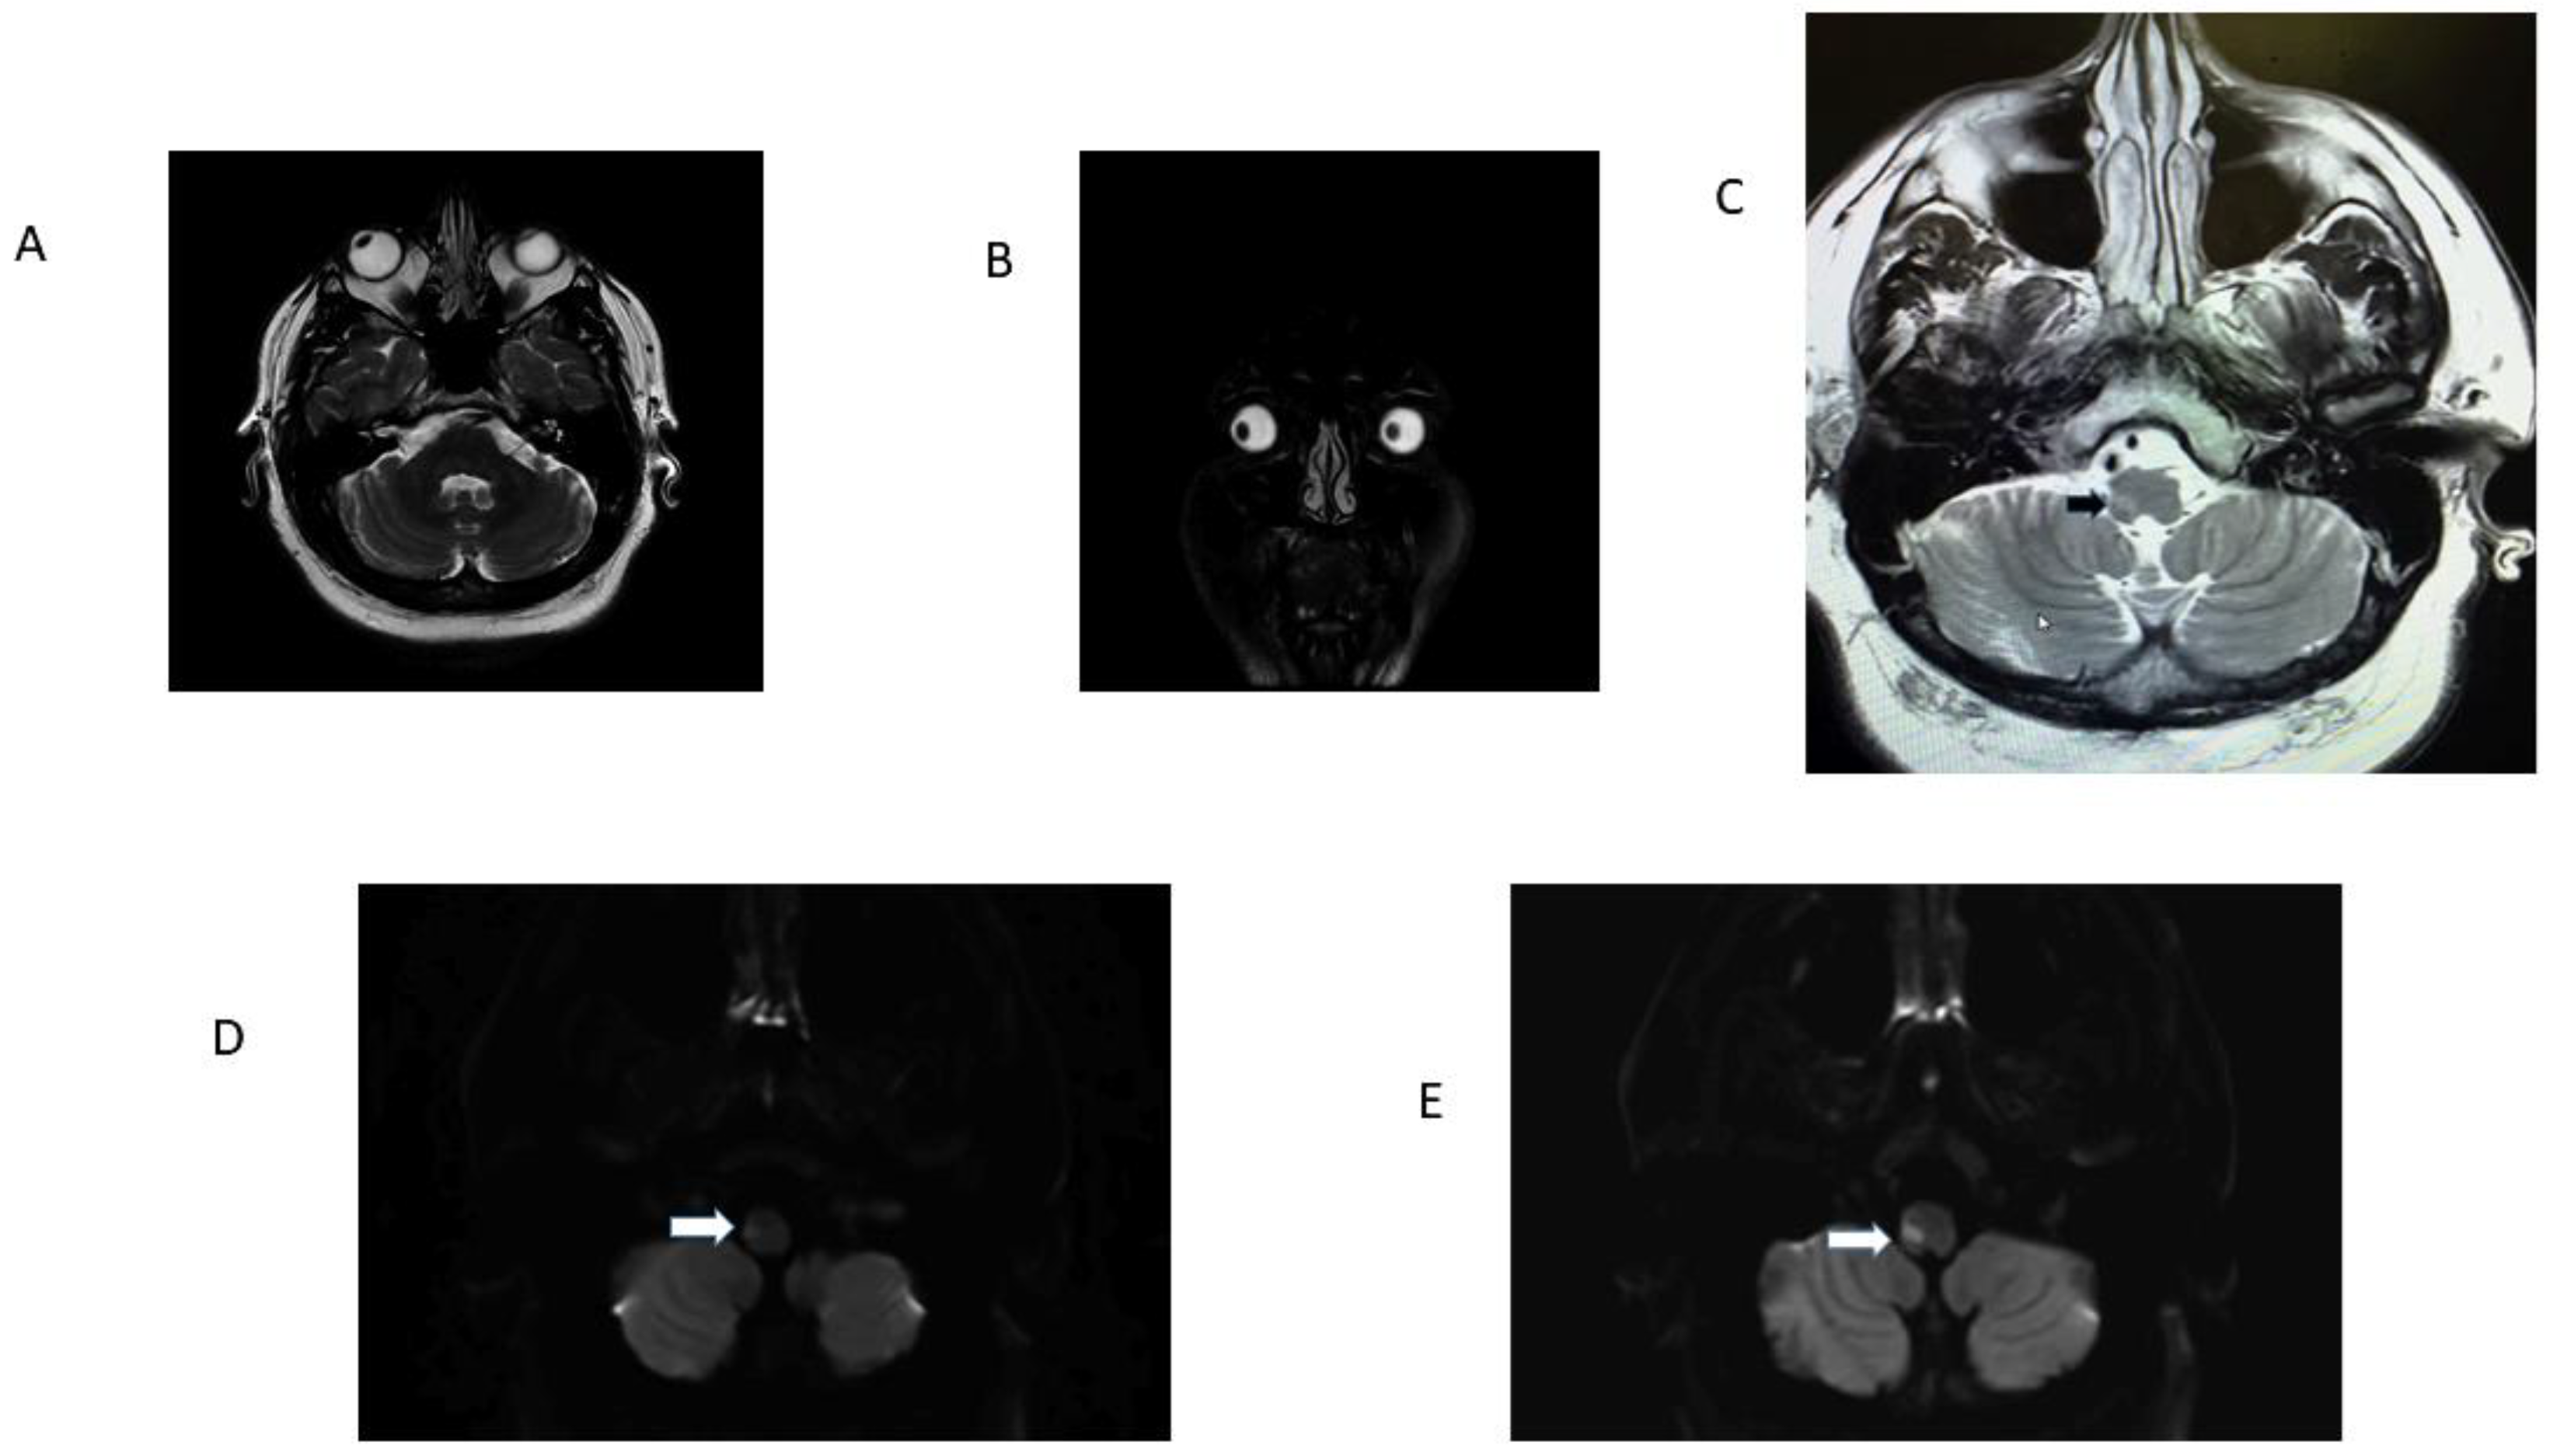

| 1 R OLD 52 | RE: 32.2 LE: 32.2 Hypometric saccades | R lateral medulla, cerebellar tonsil, uvula, and nodulus. | H direction changing | Normal | No | Noted at 32 h exam; present 6 weeks later. Resolved between 6 weeks and 5 months | Ataxia grade 3 to right |

| 2 R OLD 75 | RE: 21.9; LE 22.4. Hypometric saccades | R lateral medulla and lateral cerebellum. | H second degree to L | Normal | Ocular tilt reaction | Noted at 30 h exam; present during hospital stay for 3 days. | Ataxia grade 3 to right |

| 3 L OLD 88 | RE: 22.4; LE 26.6 Single rapid corrective saccades | L lateral pons, mid basilar stenosis. | H second-degree L | Abnormal | No | Noted at 24 h exam. Present for 5 days in ICU until cardiac arrest. | Ataxia grade 2 to left |

| 4. L OLD 61 | RE: 25.9; LE:30.3 Hypometric saccades | L lateral medulla. | H second-degree R | Normal | Yes | Noted at 72 h exam. | Ataxia grade 3 to left |

| 5. R OLD 41 | RE: 34.9; LE 25 Hypometric saccades | False-negative in initial MRI. Second MRI: stroke R lateral medulla. | Primary gaze h LBN. Did not follow Alexander’s Law | Normal | Yes | Noted at first exam and at 12 h. Resolved in 48 h. | Ataxia grade 3 to right |

| 6. L OLD 49 F | RE: 21.4; LE: 36.2 Hypometric saccades | False-negative in initial MRI. Second MRI: L lateral medulla. | H 1st-degree RBN | Normal | Yes | Not checked at first visit; present at 36 h exam; lost to f/u. | Ataxia grade 2 to left |

| 7. R OLD 62 F | RE: 13.6; L:0.1 Hypometric Saccade | False-negative in initial MRI. Second MRI: stroke R lateral medulla. | H LBN second degree | Normal | yes | OL Noted at 24 h exam, resolved in 12 h. | Ataxia grade 3 to right |

| 8 R OLD 63 M | RE: 29.3; LE: 27.35 | R lateral medulla. | Second-degree torsional to L shoulder/h-RBN | Normal | OTR | Noted at 32 h exam. | Ataxia grade 3 to right |

| 9 R OLD 51 M | RE: 35.6; LE 26.6 | False-negative in initial MRI. Second MRI: stroke R lateral medulla. | UBN | Normal | yes | Noted at 48 h exam. | Ataxia grade 3 to right |

| 10 R OLD 59 M | RE: 45.3, LE: 42.3 | R dorsolateral medulla. | Bilateral h gaze-evoked nystagmus | Normal | Yes | OLD at 6 h | Ataxia grade 2 to right |

| 11 R OLD 28 M | RE: 35.6, LE: 20.9 | R lateral medulla and cerebellum. | H LBN torsional top pole to left shoulder. | Normal | No | OLD at 24 h. | Ataxia grade 3 to right |

| 12 L OLD 39 M | RE: 22.4, L: 18/1 | L lateral medulla and cerebellum. | H RBN in center fixation, h-gaze-evoked nystagmus. | Normal | No | OLD at 24 h. | Ataxia grade 3 to left |

| 13. R OLD 45 M | RE:40, LE: 34.4 | R lateral medulla. | No nystagmus. | Normal | No | OLD at 6 h. | Ataxia grade 3 to right |